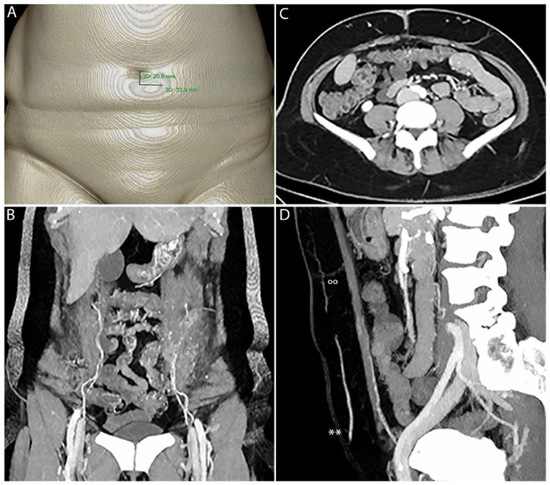

Figure 1.

CTA enables fast 3D PM with clear delineation of SP, P, F, M and the IEA. SP must be measured manually in relation to the umbilicus (A). (B) shows PM in 3D. The origin of the IEA, including M with type II branching on the left and type I branching on the right, is clearly visible. In (C), F and P of the perforators on the left and right side are clearly visible. IEA, M, F, P(°°) and SP can be clearly seen within the sagittal view (D), including the superficial epigastric artery (SIEA**).

All patients underwent CTA, according to our standard protocol (Table 2). After intravenous administration of iodinated contrast agent followed by a 30 mL saline chaser, scans were started with a delay of 30 s after passing the predetermined threshold of 150 HU within the abdominal aorta. Locations of SP, F and M were measured by distance from the umbilicus for presurgical planning and intraoperative transformation (Figure 1, Figure 2 and Figure 4). Perforators were transposed on dedicated 3D volume renderings showing the ventral abdomen.

2.3.1. Precision of Perforator Mapping